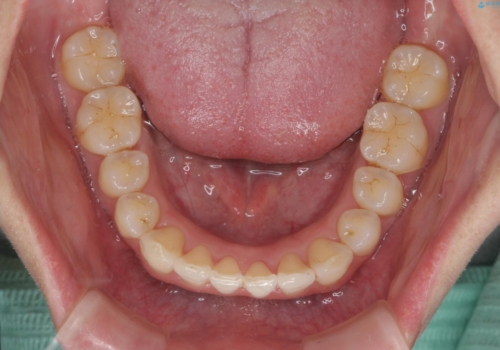

インビザライン で治す 出っ歯の治療

- 前歯の突出感、出っ歯の治療を希望され来院されました。

インビザラインを用いた治療計画を立て、しっかりと出っ歯を治すためにマイクロインプラントを併用します。

マイクロインプラントを併用することでしっかりとマウスピース全体を後方へ引き、前歯の突出感を改善することができました。